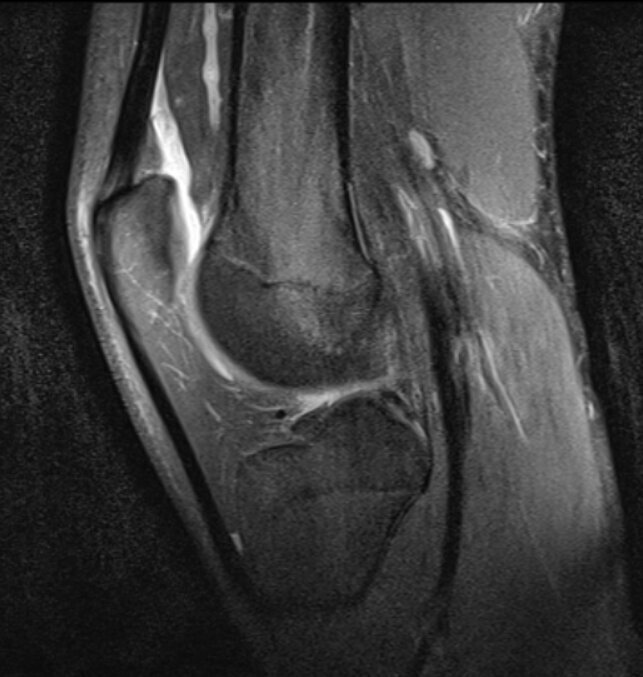

Плоскости изображения:

- Фронтальная.

- Аксиальная.

- Сагиттальная.

Коленный сустав в сагиттальной плоскости.